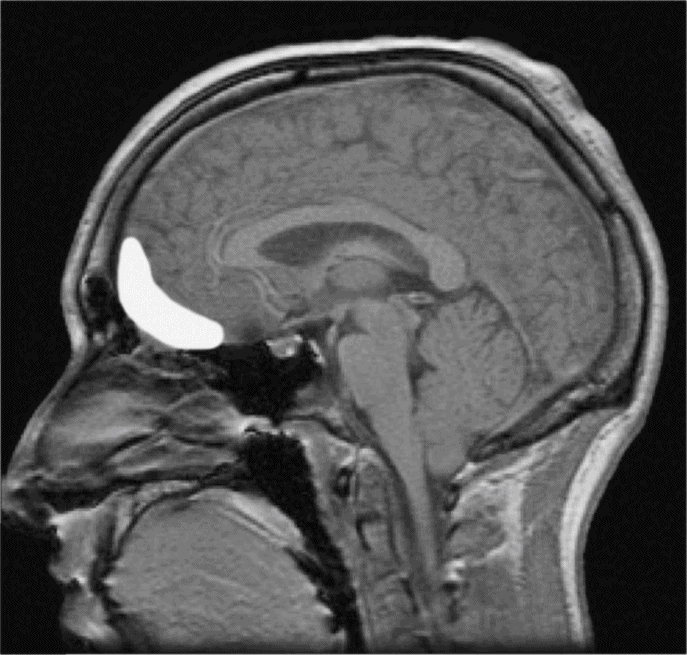

答案很明显,手术没有损害他的智商,却夺去了他体验情绪的能力。手术损害了一个叫“眶额皮层”(orbitofrontalcortex,OFC)的重要部位。该部位在眼睛的后方、大脑额叶的下面,如果你一根手指按住太阳穴,另一根手指指着眉心,指尖连线的交点就是。